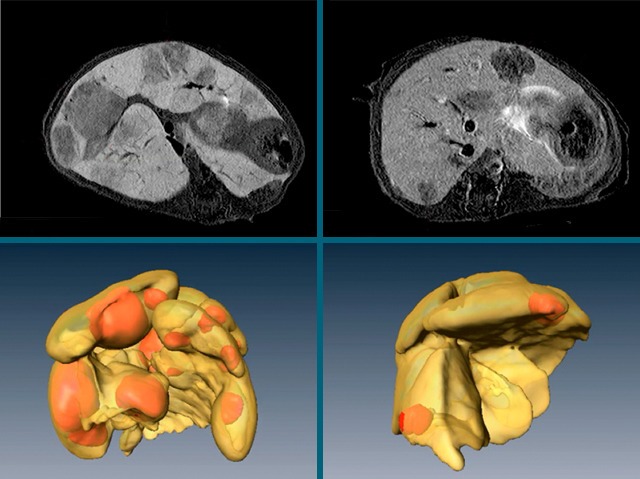

Liver cancer is the third most common cause of cancer death worldwide, particularly in the developing world. More than half of all liver cancers are due to infection with the hepatitis B virus, which causes years of damaging inflammation that in some cases eventually results in tumours. Tiny fragments of cells called platelets flock to areas of damaged liver, releasing chemicals that stimulate further inflammation. To try and break this vicious cycle, researchers are investigating ways to stop platelets from releasing their deadly cargo in mice with hepatitis-induced cancer. The liver in the left-hand panels, packed with multiple tumours (darker blobs), is taken from an animal treated with a placebo. While the organ on the right is from a mouse given two cheap anti-platelet drugs, aspirin and clopidogrel, and has far fewer tumours. The next step is clinical studies, to see if these promising results bear up in humans.